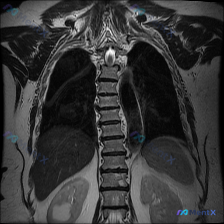

整理到一份有意思的影像对照材料: 一张胸部MRI T2加权像(冠状位),原始影像分析写的是: - 肺野、纵隔、胸壁未见明显病理改变 - 「胸椎排列整齐」,骨质结构完整 - 未见明显异常占位、渗出或积液 但有临床视角直接提出:这张图能看到脊柱侧弯。 后面附的深度分析也指出了几个点: 1. 仅看这张切面...